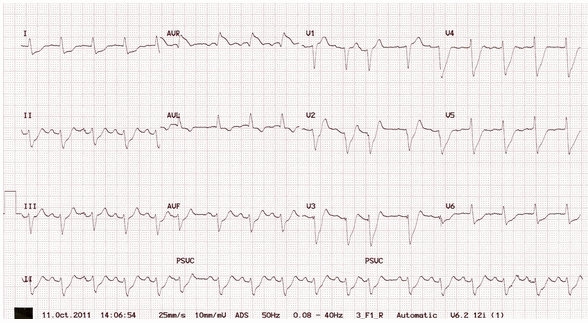

Ví dụ điển hình của tác LMCA:

ST chênh xuống phổ biến, nổi bật nhất của các đường dẫn bên (V4 - 6, I, aVL).

ST chênh lên > 1mm trong aVR.

ST chênh lên trong aVR ≥ V1.